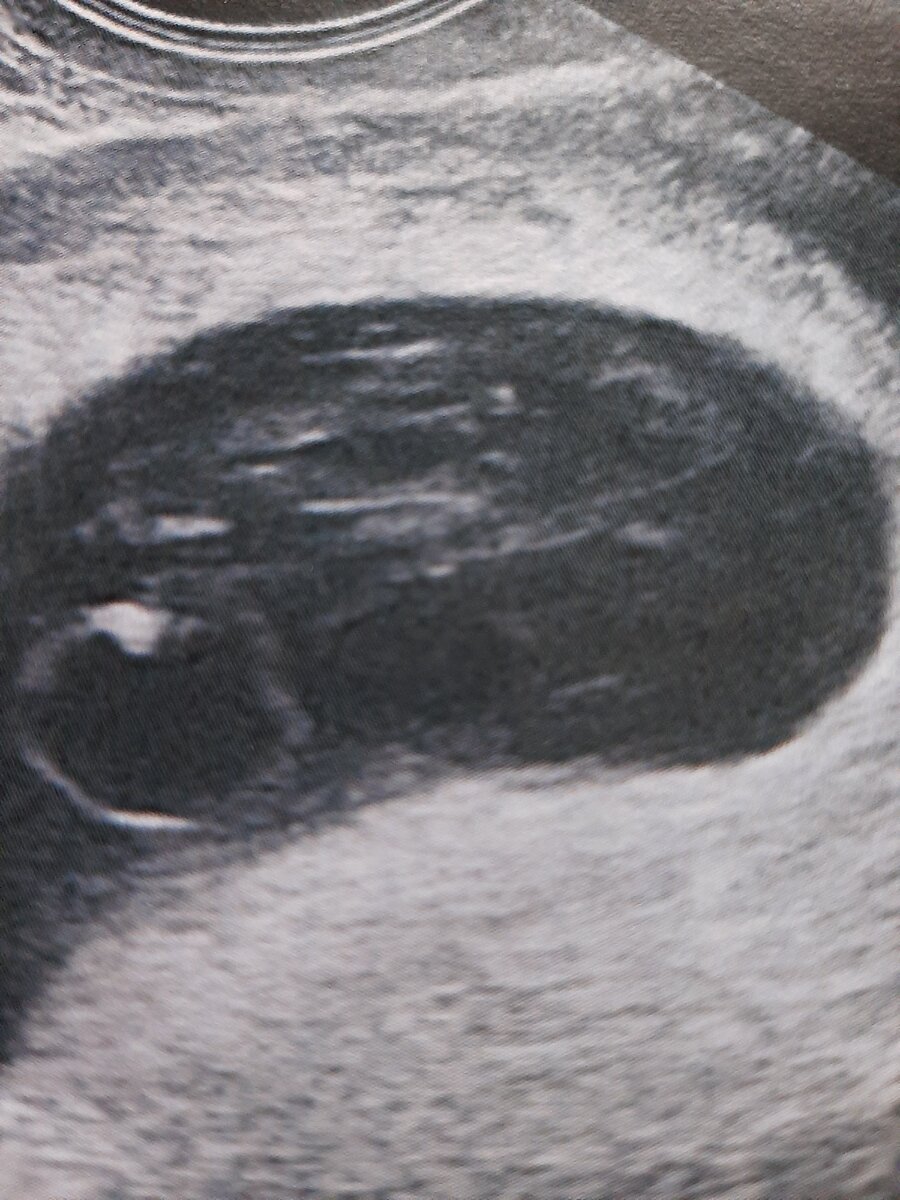

Анэмбриония. Плодное яйцо каплевидно деформировано, не имеет содержимого. Фото любезно предоставлено кафедрой лучевой диагностики

На экране видим вокруг плодного яйца различной формы и размера анэхогенные ( то есть-черные))) участки.